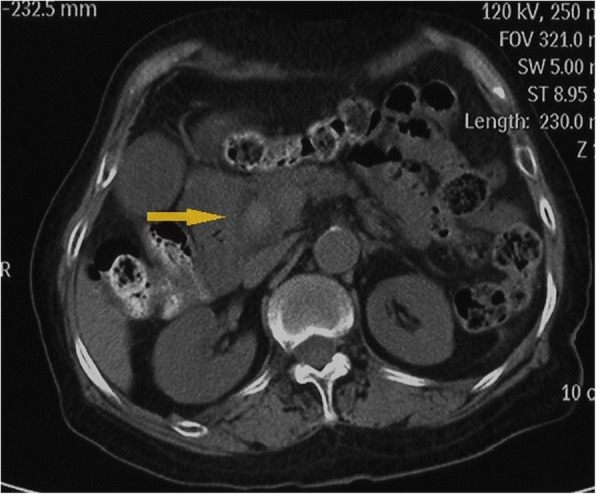

A high-density image of the middle CBD with a markedly dilated biliary tree was revealed on the second CT (Fig. 3). Thus, ERCP was repeated. A long filling defect was noted in the dilated common bile duct (Fig. 4), and a blood clot (maximum diameter 35 mm × 10 mm) was extracted with a basket (Fig. 5). Then, an endoscopic nasobiliary drainage (ENBD) tube was inserted into the CBD to ensure continued biliary drainage. Two days later, her temperature returned to normal, and abdominal pain was relieved. Histopathological examination revealed massive red blood cells with white blood cells and tissue necrosis (Fig. 6). After the treatment, she recovered and was discharged without any other complication.